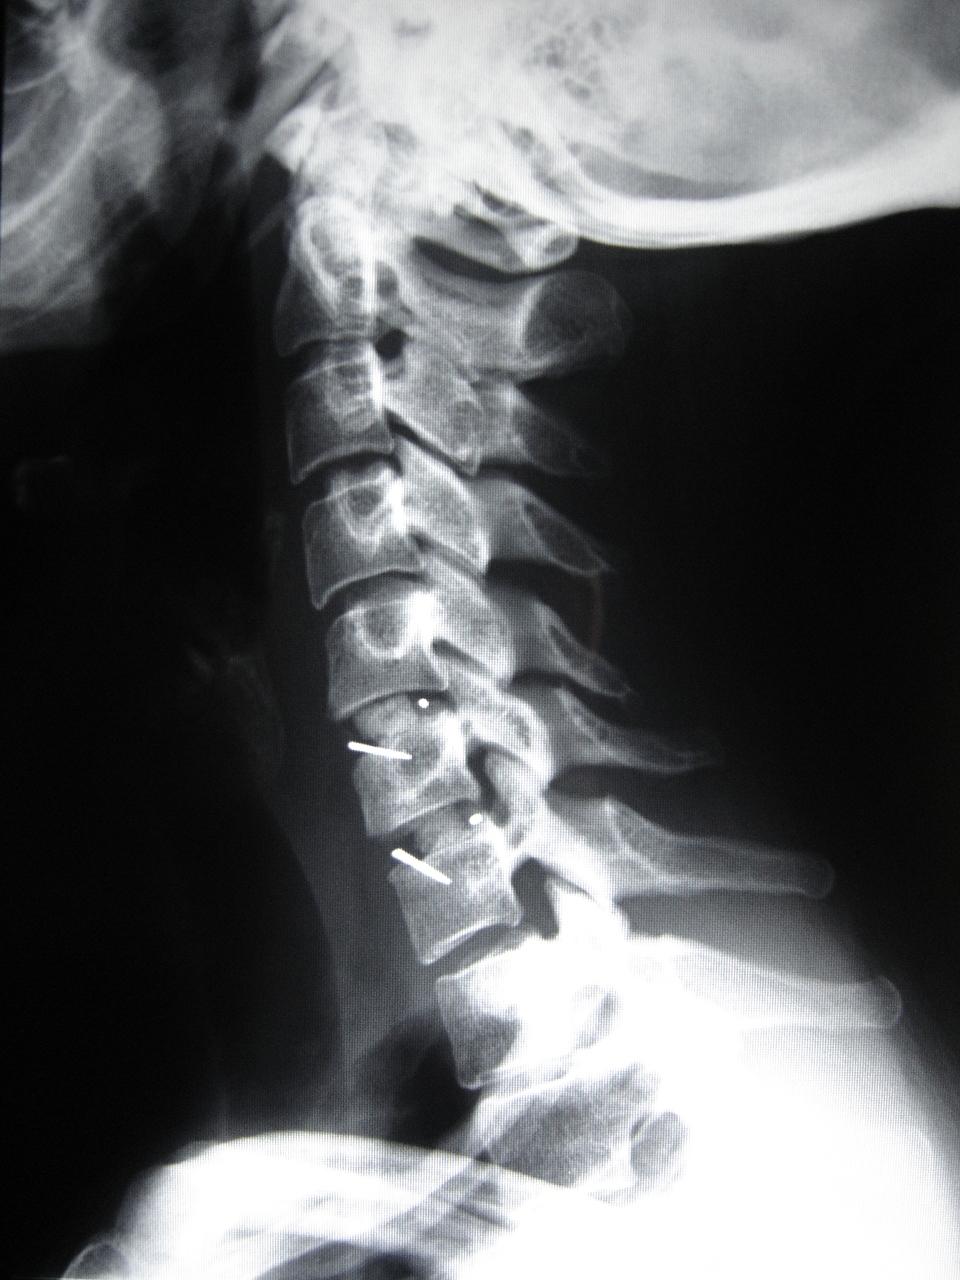

Ao lado, imagem de raio-x evidenciando Artrodese cervical de dois níveis com colocação de espaçadores “cages”, com enxerto ósseo.